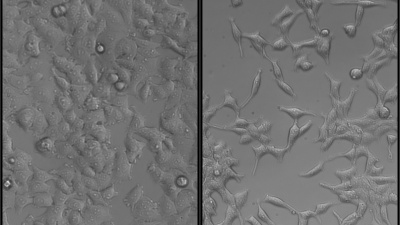

Blood platelets can "feel" the physical environment around them, researchers have learned.